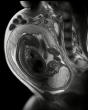

Descoperire epocală dintr-un plan divin al creatiei: Celulele fătului trec prin placentă și vindecă bolile mamei. Celulele mamei trec la făt și se instaleaza in creier permanent

Oamenii de știința au examinat creierele a 59 de femei dupa decesul acestora, cu varste cuprinse intre 32 și 101 ani. La ...